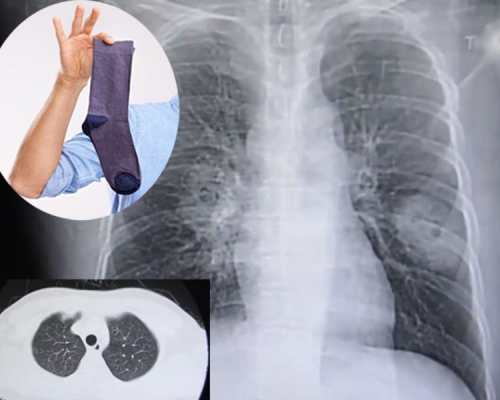

男子肺部感染真菌愈趨嚴重 自爆喜歡聞臭襪

福建漳州一間醫院接收了一名38歲的彭姓男病人,病人的症狀是咳嗽,胸悶,從醫院的X光片影像診斷是患上肺炎,但是經過一個星期的治療後,該男子的病情不但沒有好轉,並且有惡化的症狀,醫院對該男子進行肺部穿刺檢查,確診該男子是肺部受真菌感染。直至醫生與該男病人溝通後,發現他有喜歡聞臭襪的怪癖!

據報,該男子家庭生活條件還不錯,生活環境也很好,自己身體平時也不錯,就是最近經常熬夜,加上每天照顧嬰兒,免疫力有所下降,還有就是自己有一個不好的習慣,就是每天下班後脫了鞋,會刻意的聞下自己的臭襪子,所以有可能是這個壞習慣導致了自己的肺部感染真菌,在前期治療階段導致了病情加重。

呼吸科醫生麥轉英指出,肺真菌病主要與免疫力有關,呼吸道感染的情況較罕見,不過「一旦吸入真菌量大,超過了人的機體防禦功能時,就可能發病」。麥醫生又指,病人因照顧小孩經常熬夜,導致免疫力下降,亦有可能是患病的原因。